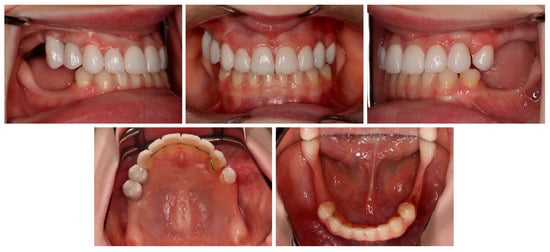

3. Results

3.1. Treatment Process

3.2. Follow-Up

| May–August 2022 | Finishing; control panoramic X-ray (Figure 8); 1st canine relationships and midline consistency; debonding of the brackets; fixed upper and lower retainers’ placement (0.027″ × 0.011″ 8-strand braided SS), tooth no. 24 was not fixed to the retainer due to increased mobility. |

| September 2022 | E-max (lithium desilicated ceramic) veneers on upper teeth; individual implant abutments (titanium pre-milled abutments) and implant-supported blocked crowns (zirconia veneered with porcelain using the cut-back technique) on dental implants; removable thermoformable retainer. |

| March 2023 | Retention phase: 10-month follow-up. Stability of treatment results; minimal opening of the spaces mesially to teeth no. 34 and 44; proper mobility of tooth no. 24. Bleaching of the lower teeth. |